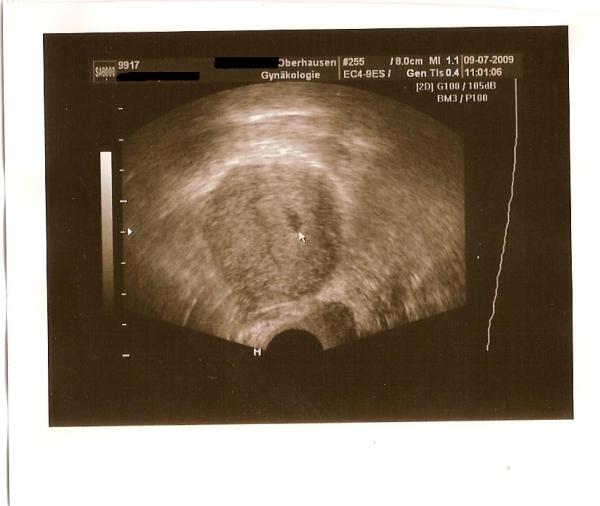

bin 6.SSW. es war ne fruchthöhle zusehen und am montag muss ich dann zum blutabnehmen. bin jetzt happy

Schöööööööön das alles in ordnung ist Bei mir war gestern auch nur eine Fruchthöhle zu sehen,hänge das bild mal an. lg Steffi mit Vicky an der Hand und Bauchzwerg inside

Bild zu